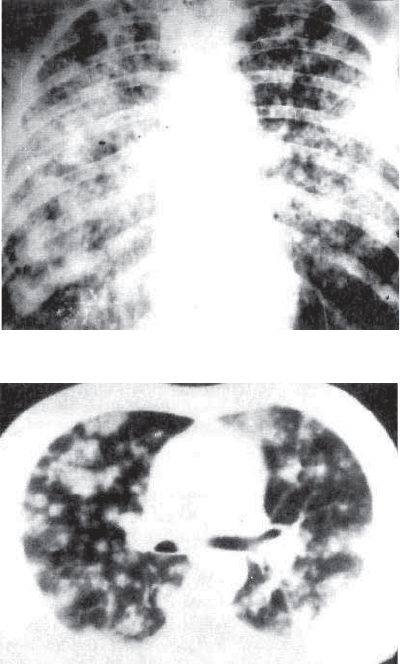

Рентгенологическое исследование наряду с увеличением внут*

ригрудных лимфатических узлов выявляет наибольшее скоп-

ление очагов в средних и нижних отделах легких. При брон-

стояние больных обычно прогрессивно ухудшается. При рент-

генологическом исследовании выявляют густую мелкоочаго*

198